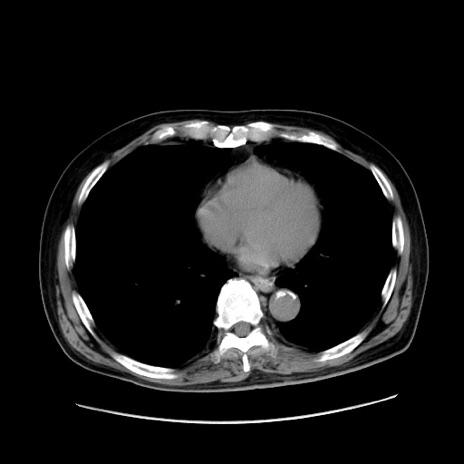

症例30(横断像)

【症例】80歳代男性

【現病歴】約6時間前から臍下部痛が出現。次第に腹部膨隆・背部痛も生じてきたため来院。背部痛の場所は変化しない。

【身体所見】意識清明、BT 36.3℃、BP  131/87mmHg、P 87bpm、SpO2 100%(RA)、臍周囲自発痛・圧痛あり、反跳痛なし、自発痛部位に一致して板状硬あり、腹部膨隆、腸雑音減弱、CVA tenderness両側陰性。